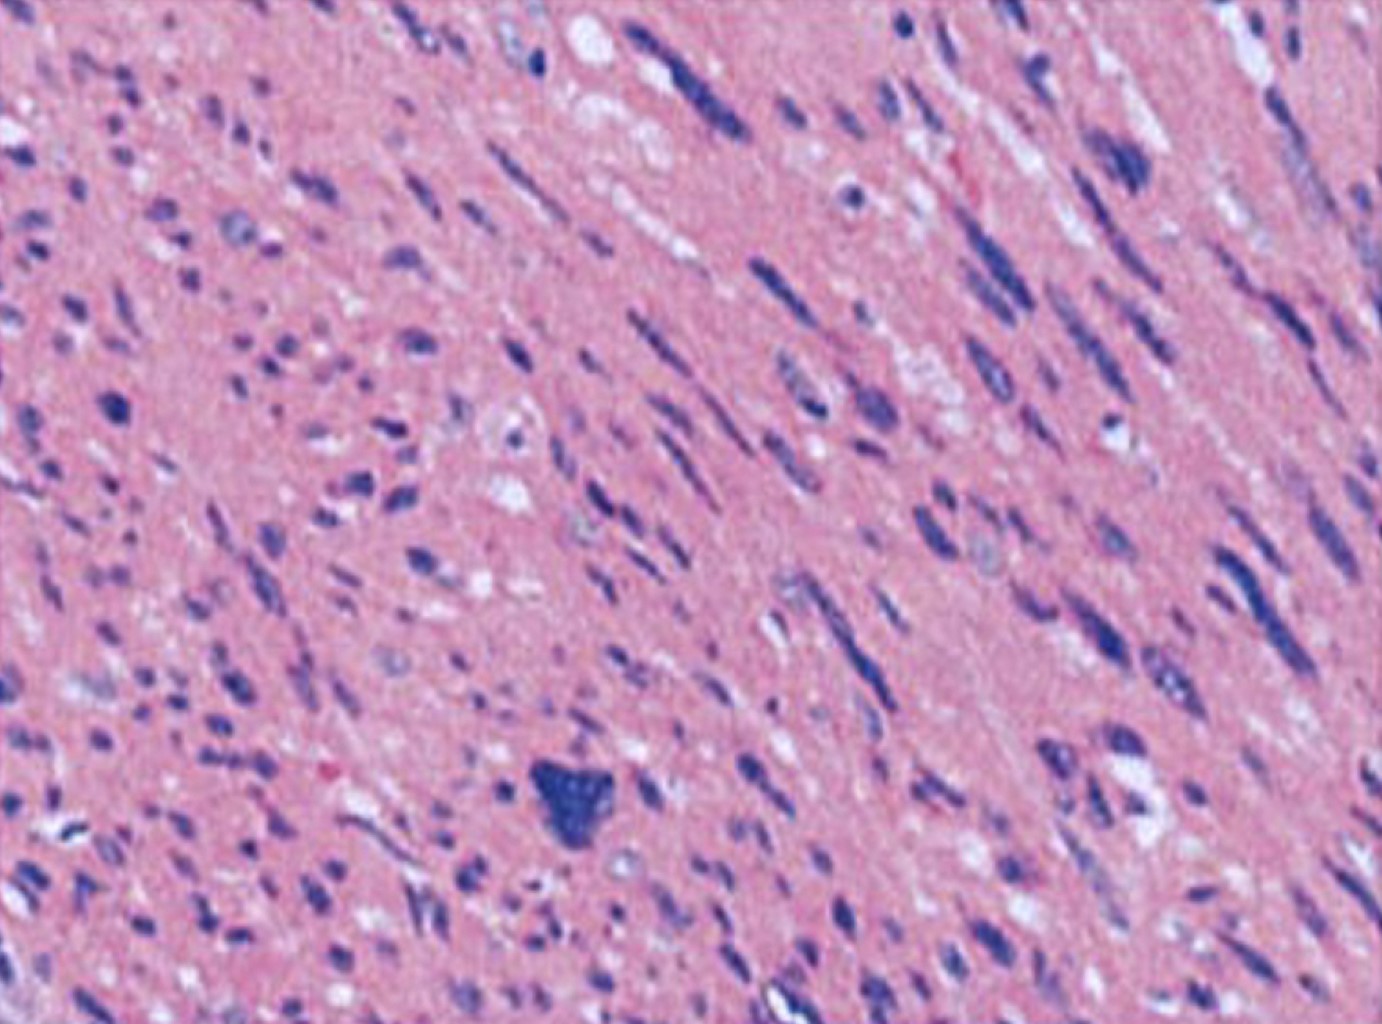

Radial nerve schwannoma

Introduction: Schwannomas are benign nerve sheath tumors that are rare in the radial nerve. Case report: a 62-year-old man presented with a mass in the distal right radius with a 5-year history of progression and associated paresthesias. Ultrasound revealed a well-defined, heterogeneous, and vascularized lesion. Surgical resection was performed without complications, and histopathology confirmed a schwannoma. Conclusion: due to its slow growth and encapsulated nature, the ideal treatment is complete excision. This case highlights the importance of early diagnosis and appropriate surgical management to prevent neurological sequelae.

Figure 1

Figure 2

Figure 3